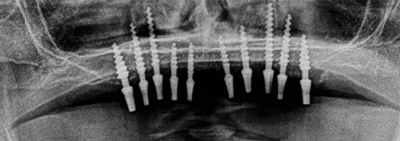

Tilting of dental implants in the posterior region of the jaw has been demonstrated as an alternative to bone grafting for atrophied jaws. A tilted distal implant can allow a longer dental implant to be used and a more posterior implant position to be achieved. The theory here is that greater distances between the anterior and posterior implants would better distribute occlusal forces; thus, the transverse force placed on the tilted implants would not be detrimental to them. In the maxilla, the distal implants also could benefit from the cortical bony walls of the sinuses and nasal fossae. Therefore, implants can be placed in tilted instead of axial orientations to engage the residual cortical bone in all directions, such as in the palate, anterior and posterior walls of the maxillary sinus, and maxillary tuberosity.23,24 Tilted implants with various macro designs can also adapt to nonalveolar anatomical bone in the paranasal/interantral and pterygomaxillary regions and the zygomatic bone (Figure 3).11,13,25

Fig 3. Tilted implants can adapt to nonalveolar anatomical bone in the interantral and pterygomaxillary region to avoid a sinus graft procedure.

Figure 3